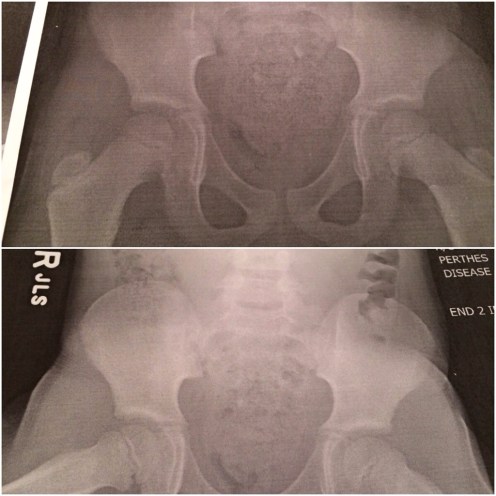

Soon after the neighborhood gathering (which was so much fun)… I was supposed to head up to the track meet but I took my 3rd daughter to the Insta-care for an X-ray appointment to check out her leg. She has the symptoms of Perthes Disease… The doctor took x-rays of her (the Doc was so amazing and so good with my daughter)!

They checked out her x-Ray and ruled out Perthes disease! π I was relieved! The lady printed off my daughter’s x-Ray and gave her a copy. She was so excited!

On Monday Dr. Fullmer will check out a few more things… But it is looking hopeful. π I just hope to find the reason why to often of nights my daughter is very close to tears or in tears because of the pain in her right leg. π¦ Or know the cause of her stiff legging it while she is running (or limping). Maybe it is major growing pains…?